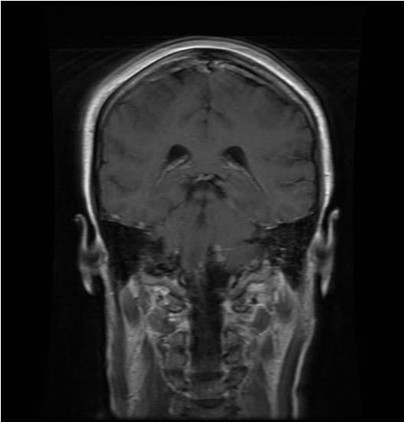

病例二:王**,男性,53岁。因做小脑肿瘤术后9年,头痛头晕,伴颈部疼痛、走路不稳半年入院。入院诊断:延颈交界血管网织细胞瘤。术式:后正中入路延颈交界区血管网织细胞瘤切除术。术后病理:血管网织细胞瘤。术后头痛头晕,颈部疼痛消失,走路平稳。

术后